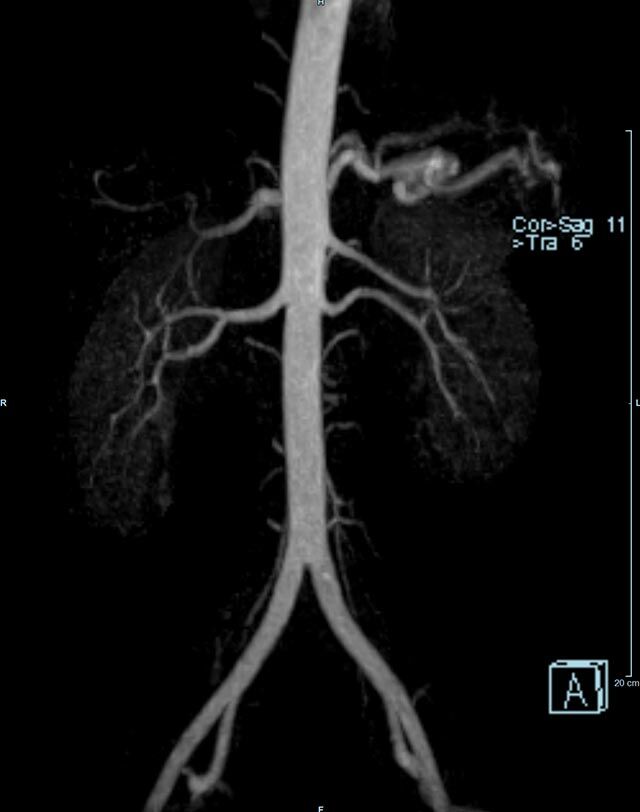

Aorta

• Bauchgefäße

• Erfassung und Verlaufskontrolle bei arteriellen Aneurysmen (Aussackungen der Arterien), vor allem der Bauchaorta

• Darstellung von Gefäßengen an Nierenarterien, Baucharterien und Becken-/Beinarterien